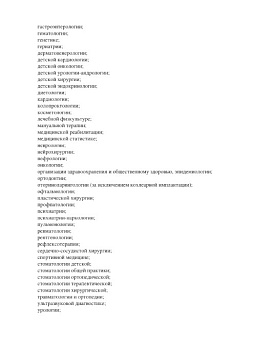

Лицензии